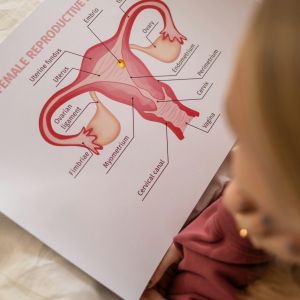

Ginecologie

Ginecologie